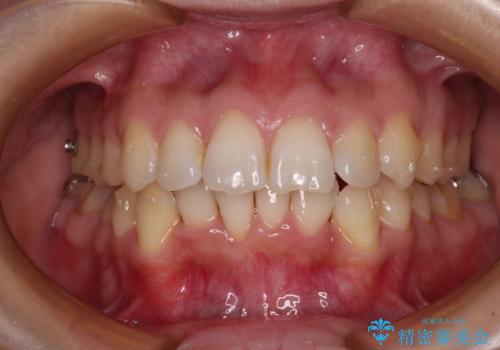

- 前歯のデコボコで前方に出ていることを気にして来院された患者様です。

上顎前歯が捻れて前方に飛び出しており、下顎前歯もそれに沿うようにデコボコとなっていました。

IPR(歯と歯の間を削る処置)によりスペースを獲得して上下顎前歯のデコボコを改善し、飛び出している前歯が引っ込むように設定し、インビザラインにて矯正治療を行うこととしました。